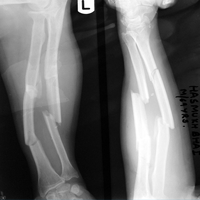

Case:6 Segmental Comminuted Fracture Radius

Patient, aged 75 years during morning walk tripped & had a fall following which he sustained injury to the left forearm. Closed reduction & interval fixation with Intra-medullary TEN nails was done in radius & ulna. Now he has full supination & pronation function of forearm.

Pre-Op

Post-Op